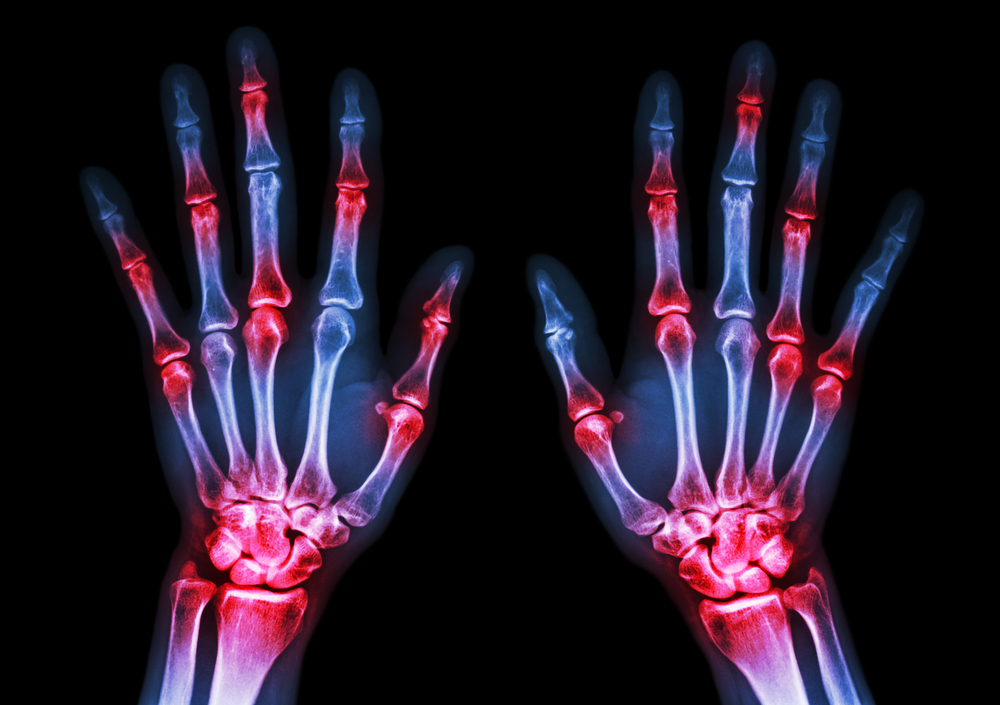

Six Surprising Facts about Arthritis

Many of us are aware that arthritis is on the rise in the US, with people experiencing stiffness and pain in the joints of their hands, feet and often throughout their bodies. In fact, the CDC reports that an estimated 78 million Americans will be diagnosed with arthritis. That’s 26% of the projected total population of people over 18 years old.

Rheumatoid arthritis is an autoimmune condition. The body’s immune system attacks the joints, which can lead to swelling, pain, loss of mobility and even joint disfigurement.